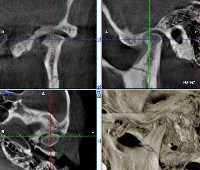

CBCT of the temporomandibular joint.

CBCT TMJ. Это метод лучевой диагностики, целью которого является исследование височно-нижнечелюстного сустава. Это исследование позволяет визуализировать следующие анатомические структуры: голова и верхняя часть нижней челюсти, нижнечелюстная ямка височной кости, суставное пространство и прилегающие костные структуры верхней челюсти. TMC сBCT дает возможность выявить следующие патологические изменения: травматическое повреждение кости, смещение суставных поверхностей, аномалии развития, дегенеративно-дистрофические процессы и новообразования. сBCT TMJ обычно выполняется без улучшения контраста. Для увеличения содержания информации сканирование выполняется в двух функциональных положениях: рот открыт и максимально открыт.

CBCT TMJ визуализирует следующие заболевания и патологические изменения: переломы или переломы костей, составляющих сустав (нижняя челюсть, височная кость, прилегающая часть верхней челюсти) - как указано структурными деформациями, целостностью, образованием фрагментов кости и их смещение. Полные или неполные дислокации проявляются смещением суставных поверхностей переменной силы тяжести. Также могут быть определены аномалии развития, на которые указывают деформации анатомических структур, изменения в размерах и соотношениях. Исследование является информативным для обнаружения инородных тел в данном районе, оценки их характера и местоположения.

CBCT TMJ может быть использован для изучения опухолей, их распространения на окружающие ткани и структуры. При аутоиммунных поражениях ВНЧС, по данным КЛКТ, определяются остеопоротические изменения, асептический некроз, деформация, сужение суставных пространств или анкилоз ВНЧС. Гематомы и абсцессы в полости сустава на томограмме проявляются расширением суставного пространства за счет скопления внутрисуставной жидкости и могут иметь связь с наружным или средним ухом сосцевидного отростка. Сравнение результатов КЛКТ в положении закрытого и открытого рта позволяет оценить общую подвижность нижней челюсти, функциональность суставов и их симметрию.